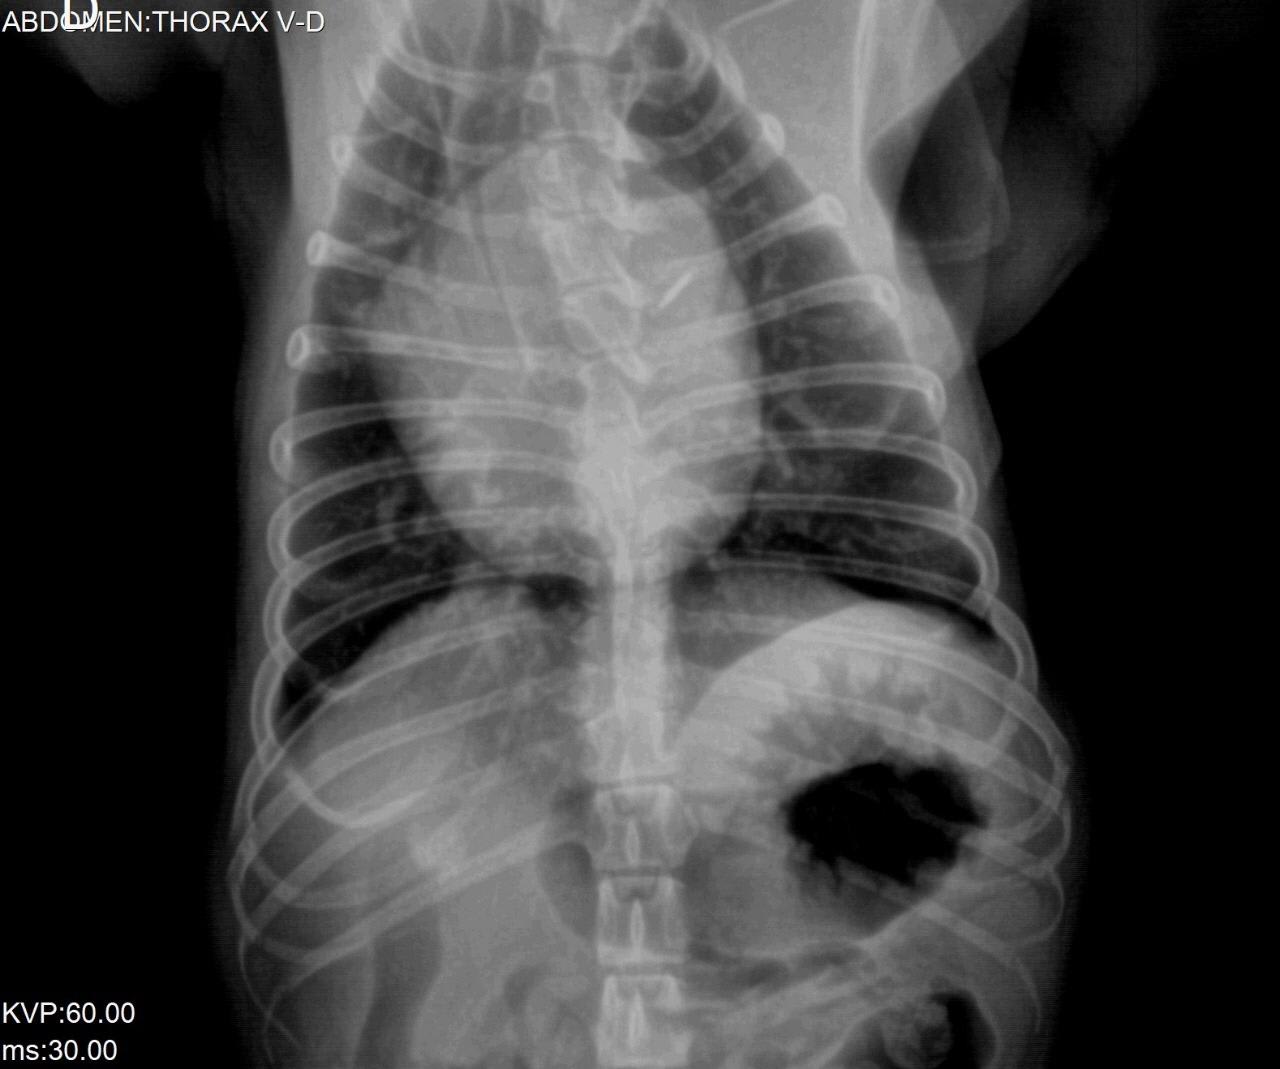

Our 2 year old french bulldog has been shivering from time to time since one week ago. We took her to the vet but want a second opinion. See images attached. We would appreciate your comments.

The hips look ok (hip dysplasia is possible on the right hip joint, but the positioning isn't perfect, which is required for that diagnosis). She does have significant issues with the vertebrae in her thoracic spine. I cannot tell exactly what is going on from these x-rays (it is much easier to evaluate them in-person), but they are likely causing significant discomfort. Lulu may need pain medications for life. A second opinion from a veterinary orthopedic surgeon would be a good idea to see if there is a surgical option to provide pain relief.